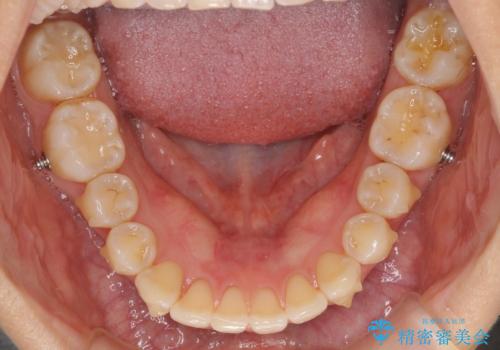

インビザラインによる矯正治療 カリエールディスタライザーを用いた奥歯の咬み合わせ改善

- 前歯の叢生と口元の閉じにくさを気にして来院された患者様です。

奥歯の咬み合わせを見ると、上顎が下顎に対して相対的に前方にありました。

口元の閉じにくさを改善するためには、上顎臼歯を後方に移動させた咬み合わせにする必要があります。

インビザライン単体で改善することも可能ですが、達成する可能性が高くないため、カリエールディスタライザーという補助装置を併用して、より確実性を上げることとしました。

奥歯の咬み合わせを改善しながら、並行してインビザラインで歯列を整えることとしました。

カリエールディスタライザーを併用したことで、確実かつ短期間で治療を終えることができました。